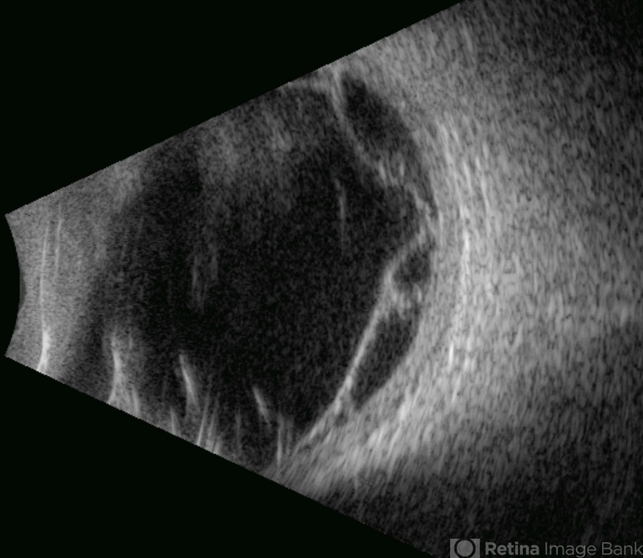

- proliferative vitreoretinopathy (PVR)

- Gustavo U. Fonseca Aguirre, Hospital Conde de Valenciana, Ciudad de México

- Ultrasonography device

- This B-mode transverse ultrasound scan depicts a post-vitrectomy eye with recurrent retinal detachment in a patient with diabetic retinopathy history. The image reveals fresh vitreous cavity hemorrhage and subretinal bleeding, along with subretinal proliferative bands (PVR strands). These findings indicate complicated tractional re-detachment with active hemorrhagic components.